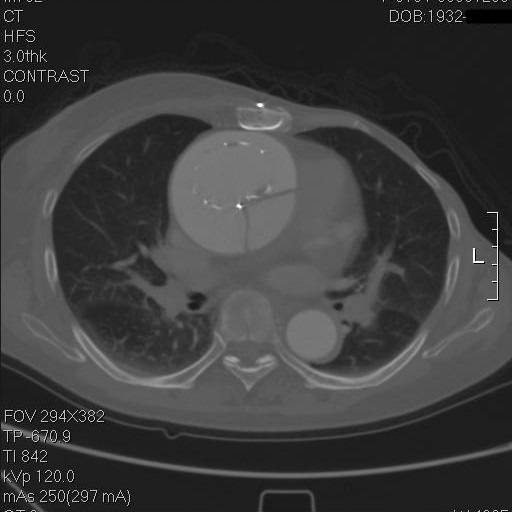

再往上,这个支架竟然是骑跨在真假腔之间的!